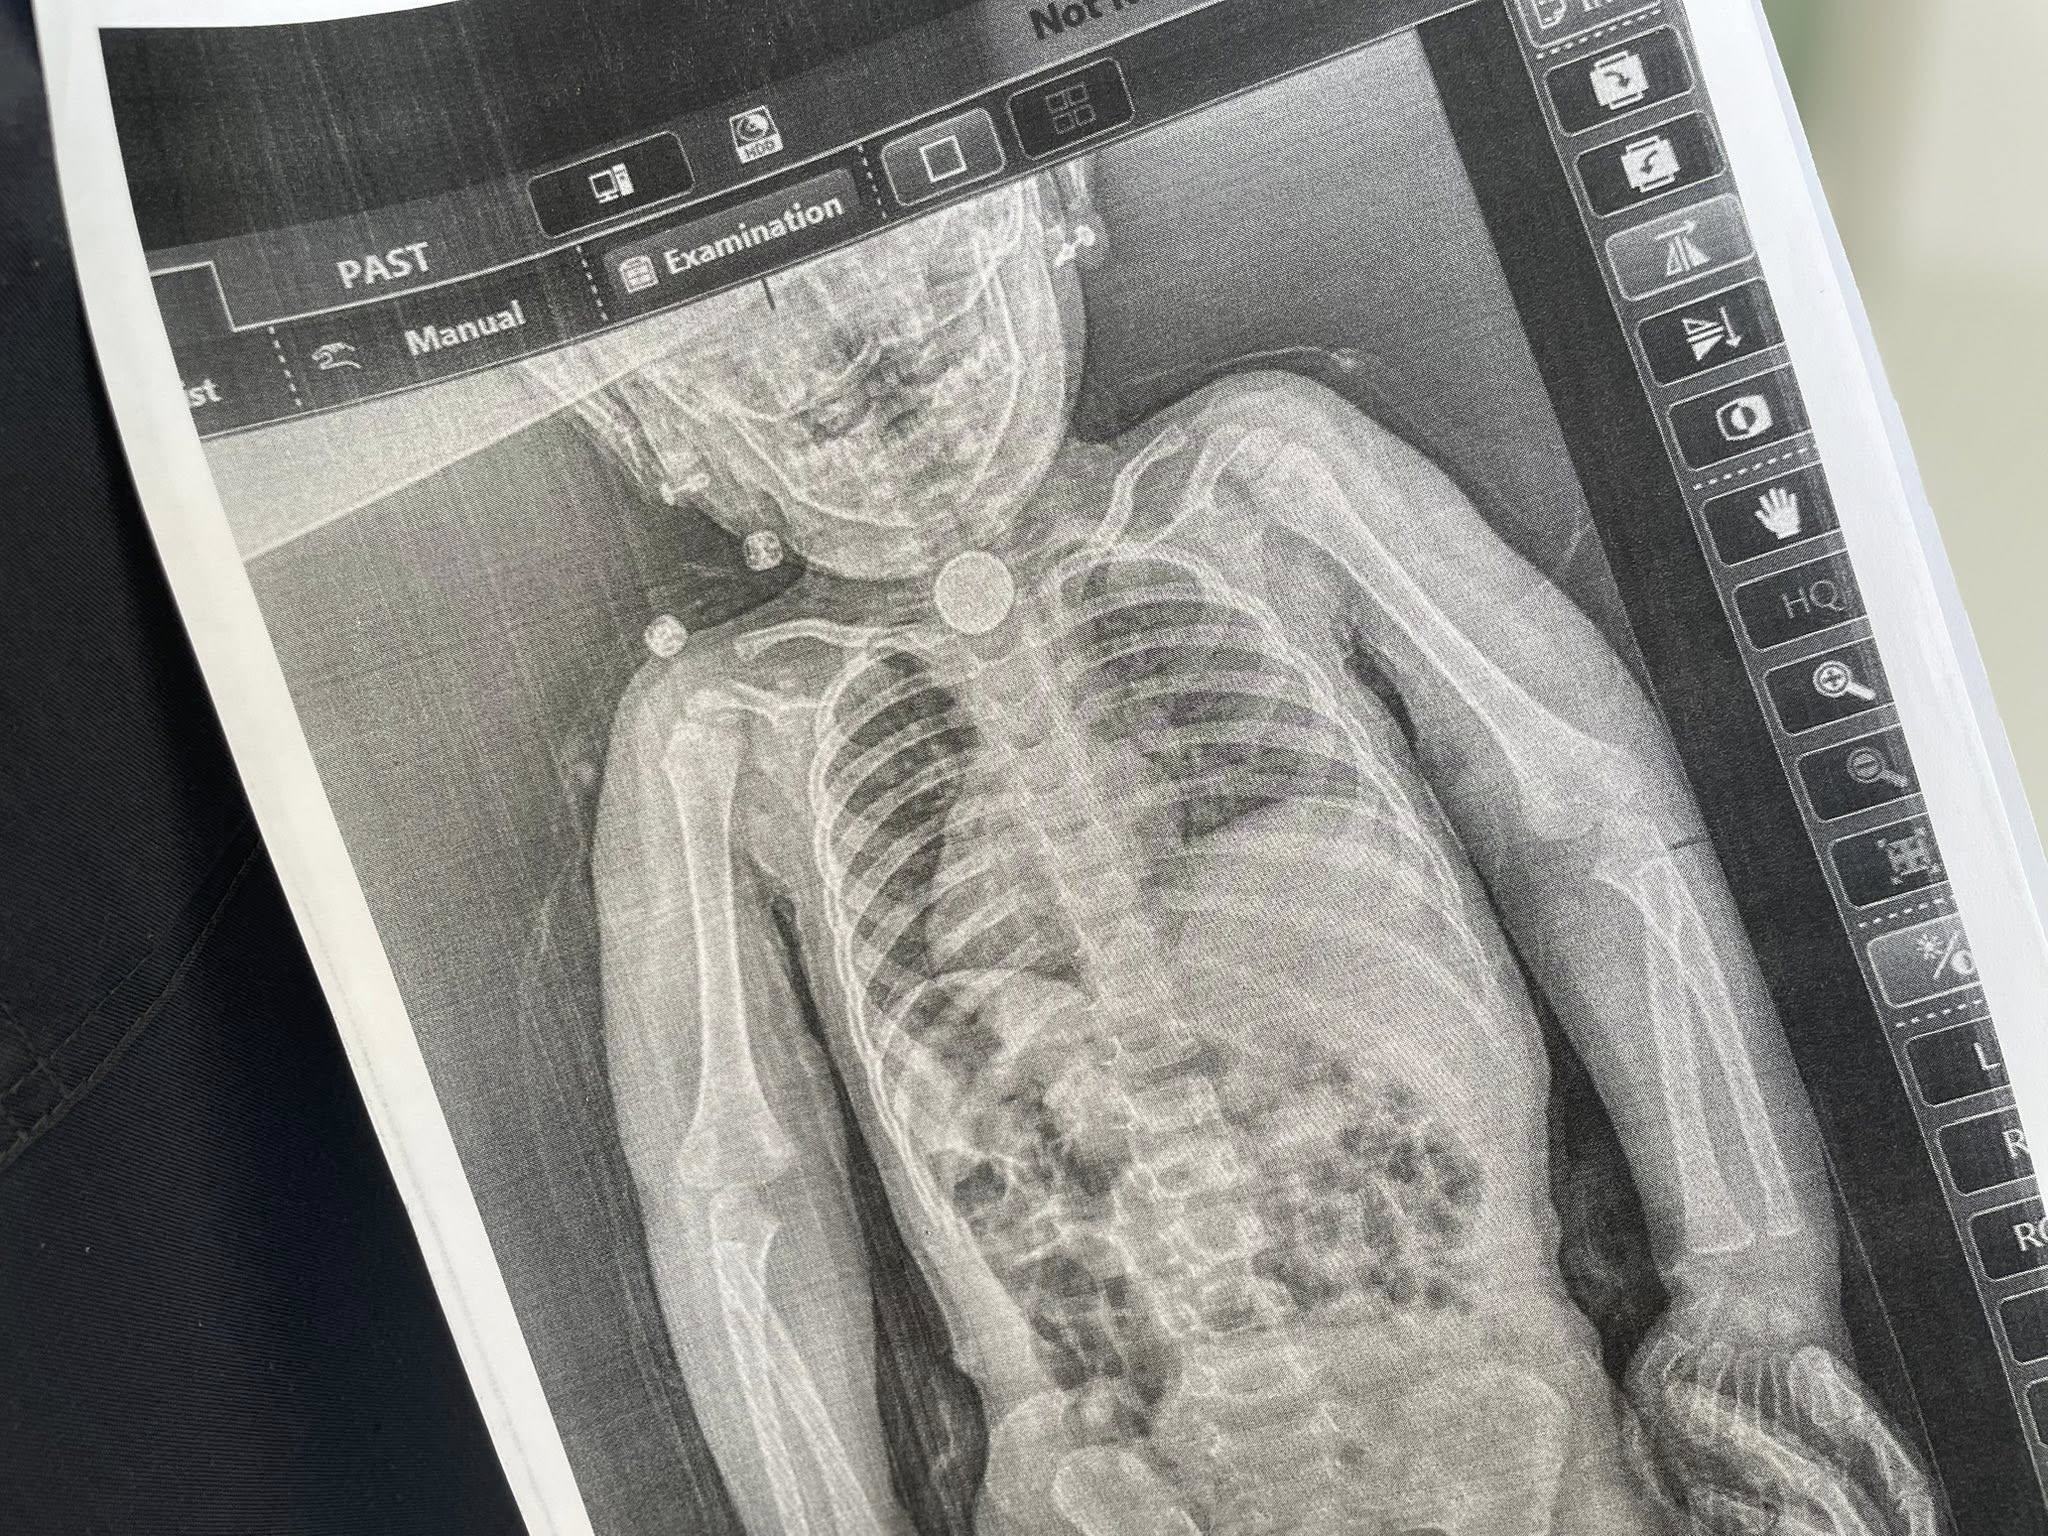

На додатковому обстеженні дівчинці зробили рентген, який чітко показав стороннє тіло у стравоході.

Виявилося, що це кругла літієва батарейка діаметром 2,5 см. Навколо неї сформувалися набряк та гіпергрануляції слизової оболонки — ознаки тривалого ушкодження тканин.